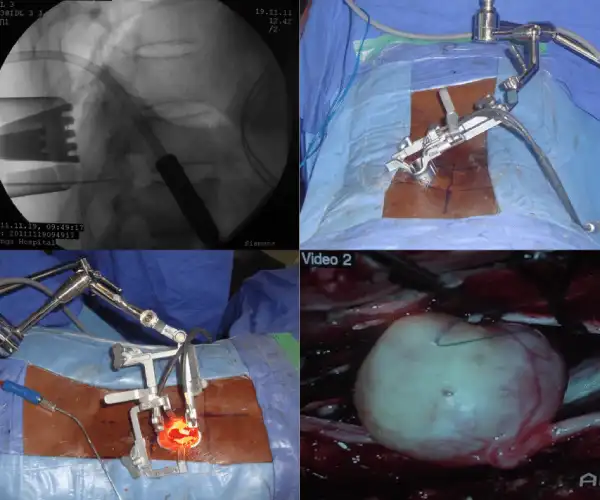

Spinal Tumour Surgery Videos

Laminoplasty for Major Tumour

Laminoplasty Surgery for Tumour

Open vs MIS tumour surgery

C2 Tumour excision, Minimally invasive spine surgery, Key hole surgery